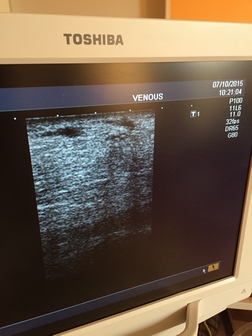

Sklerotizácia pod sonografom

Žena, 60 rokov